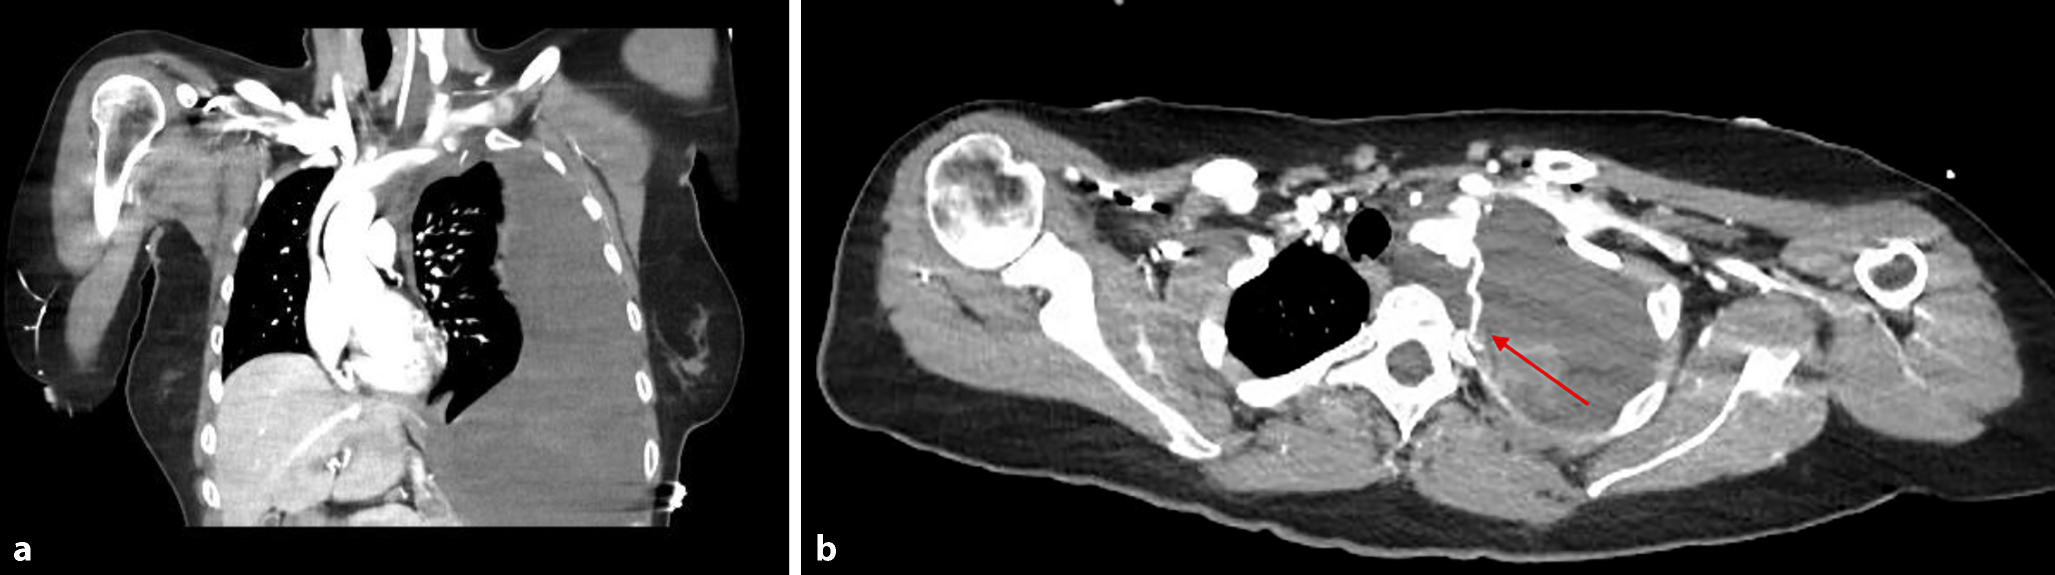

Die initiale FAST-Sonographie zeigte eine erhebliche Flüssigkeitsansammlung im linken Hemithorax. Bei Verdacht auf unklare thorakale Blutung erfolgte eine CT-Angiographie, die eine massive Hämothoraxbildung links sowie eine aktive venöse Blutung im Confluens der linken Vena jugularis interna und Vena subclavia ergab. Zusätzlich wurde ein fusiformes Aneurysma der linken Arteria mammaria interna festgestellt (Abb. 1).

Abb. 1

Die CT-Angiographie zeigte Hämothorax links (a), mit V.a. aktive Blutung bei Läsionen am Confluens der linken V. jugularis interna et V. subclavia (roter Pfeil) (b)